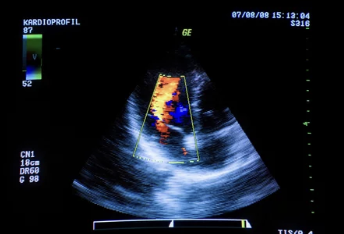

4-2. 심장 초음파(Echocardiogram)

- 심장의 구조와 기능을 확인하는 주요 검사로, 심부전증의 정확한 진단에 필수적입니다.